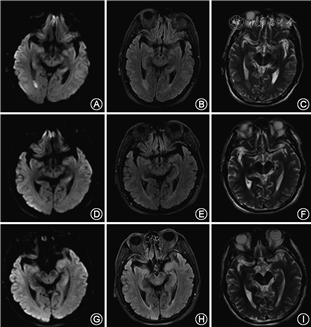

临床资料 患者男性,64岁,主因“发热、头痛、意识障碍16 h”于2019年2月9日收入东南大学附属盐城医院神经内科。患者入院16 h前无明显诱因出现发热,自服退热药物及头孢类抗生素,入院3 h前出现头痛、恶心、呕吐、烦躁不安。既往有长期饮酒史(白酒250 g/d,共30余年),一直从事养猪工作,发病前1周手部皮肤被利器损伤,伤口长约3 cm,未诊治。入院体格检查:体温38.0 ℃,心率100 次/min,血压112/68 mmHg(1 mmHg=0.133 kPa),意识模糊,反应迟钝,体格检查欠合作,左手背部伤口已结痂,双侧鼻唇沟对称,四肢肌力Ⅴ级,右侧巴宾斯基征阳性,颈抵抗,颏胸2指,克尼格征阳性。辅助检查:头胸腹部CT检查示大脑纵裂池密度稍高,胆囊炎,两肺肺气肿;血常规:白细胞14.92×109/L,中性粒细胞百分比93.3%(正常值50%~70%),淋巴细胞百分比2.3%(正常值20%~40%),超敏C反应蛋白81.84 mg/L(正常值0~10 mg/L);血清葡萄糖7.38 mmol/L(正常值3.6~5.8 mmol/L);血糖、电解质、肝肾功能、甲状腺功能、自身抗体、抗中性粒细胞胞质抗体、补体免疫球蛋白、肿瘤指标、肝炎指标、梅毒抗体、人类免疫缺陷病毒抗体均无明显异常。血培养阴性;头颅磁共振成像(MRI)示双侧侧脑室枕角信号异常,考虑感染所致可能大(图1A~C)。脑脊液检查:脑脊液压力280 mmH2O(1 mmH2O=0.009 8 kPa);脑脊液常规:混浊、潘氏试验阳性;白细胞3 522×106/L, 多个核细胞92%,单个核细胞8%;脑脊液生化:总蛋白>3.0 g/L(正常值0.12~0.60 g/L), 葡萄糖<1.00 mmol/L(正常值2.5~4.5 mmol/L), 氯化物109.56 mmol/L(正常值120~132 mmol/L;表1);革兰染色、抗酸染色、墨汁染色、肺炎链球菌抗原、单纯疱疹病毒-DNA及结核DNA均阴性。脑电图:边缘状态脑电图。心电图:窦性心动过速。入院诊断:化脓性脑膜炎。入院当天开始给予青霉素(600万单位静脉滴注,每6小时1次)抗菌、甘露醇脱水降颅压、地塞米松磷酸钠(10 mg静脉滴注,1次/d)抑制免疫反应等治疗。入院第3天患者体温恢复正常,意识转清,脑脊液血平板上过夜培养后见圆形凸起、表面光滑湿润、边缘整齐、呈α溶血的可疑菌落生长,经法国生物梅里埃公司的VITEK-2 Compact系统鉴定显示猪链球菌2型(图2),药敏试验(贴药敏纸片法)提示对青霉素、左氧氟沙星、头孢吡肟、利奈唑胺及万古霉素敏感,对红霉素、克林霉素及四环素耐药,头孢曲松中介,立即加用左氧氟沙星抗感染治疗。此后每2~5天复查脑脊液,各项指标明显好转(表1)。

患者于入院第17天再次出现发热,体温最高38.8 ℃,继续完善甲型流感病毒、乙型流感病毒、呼吸道7种病毒、肺炎支原体、肥达反应等检查,均为阴性。入院第18天复查头颅MRI:双侧侧脑室枕角信号异常,较前缩小(图1D~F)。脑脊液检查:脑脊液压力75 mmH2O;脑脊液常规:清亮、潘氏试验阴性;白细胞 41×106/L,多个核细胞5%;脑脊液生化:总蛋白0.9 g/L,葡萄糖2.00 mmol/L,氯化物118.03 mmol/L,排除化脓性脑膜炎复发可能。患者反复发热,诉双侧耳前下疼痛,体检可触及肿物,腮腺CT示双侧腮腺腺体致密,耳鼻喉科会诊考虑合并厌氧菌感染的化脓性腮腺炎可能,故停用青霉素及左氧氟沙星,调整为头孢吡肟。入院第24天体温恢复正常,诉双耳听力减退,查纯音测听提示双耳混合性耳聋。发病3个月后随访,患者仍有双耳听力重度障碍,复查头颅MRI(图1G~I)及脑电图均未见异常;发病6个月后随访,仍遗留双耳重度听力障碍伴阵发性耳鸣,听觉诱发电位示双耳听觉诱发电位消失(图3A),纯音测听提示双耳混合性耳聋(图3B),耳声发射检查双耳未引出(图3C)。

猪链球菌脑膜炎的平均潜伏期为1.0~4.8 d[4],临床表现包括发热、头痛、呕吐、颈项强直、意识障碍、头晕、前庭功能障碍和共济失调[1]。头颅CT和头颅MRI可无明显异常。部分患者MRI可见脑膜强化、脑沟脑回内高信号,脑室炎者可见脑室壁在T2加权像上呈高信号,细胞碎屑在弥散加权成像、液体衰减反转恢复序列、T2像上均可见侧脑室角内液体平面[7, 8]。脑脊液常规、生化、培养和血培养是最重要的确诊方法。典型的脑脊液检查示压力增高、外观混浊、白细胞数增多,多个核细胞为主,蛋白增多,葡萄糖和氯化物降低。2015年一项对711例猪链球菌脑膜炎的荟萃分析结果显示,患者脑脊液平均白细胞数为1 920/mm3,蛋白2.4 g/L,葡萄糖1.09 mmol/L[9]。脑脊液培养、微生物鉴定药敏试验可明确血清型、基因型、指导抗感染方案。本例患者脑脊液外观混浊、白细胞数和蛋白均超过平均数,提示由白细胞、细胞碎屑、蛋白组成的脓液稠厚,以至于MRI上可见脓液沉积。本例患者多次血培养均未发现致病菌,可能与患者血培养前已使用头孢类抗生素有关。